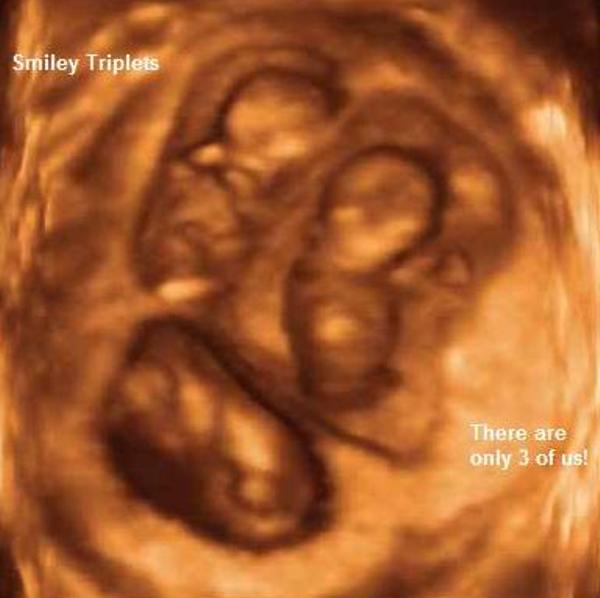

De szuperek az uh képek

Gratula a kiscsajszihoz. Nagyon édes, ahogy integet